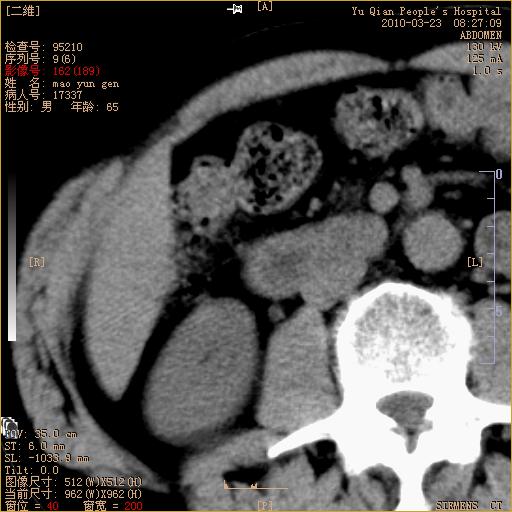

标题: CT25266:消瘦月余,前来肝部检查,请看看肠腔 [打印本页]

标题: CT25266:消瘦月余,前来肝部检查,请看看肠腔

肝区结肠占位,腺癌可考虑,建议肠镜活检。

升结肠肠壁增厚,不均强化,考虑升结肠腺癌可能性,建议肠镜检查。

1)考虑升结肠癌。2)右肾小囊肿。